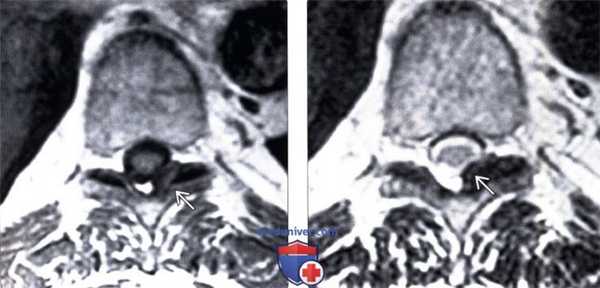

(Слева) Т1 -ВИ, аксиальный срез: признаки фокальной оссификации желтой связки, выглядящей как низкоинтенсивное образование, связанное с левым дугоотростчатым суставом.

(Справа) Т2-ВИ, аксиальный срез: односторонняя гипоинтенсивная оссификация левой желтой связки, вызывающая умеренное сужение латерального отдела спинномозгового канала и межпозвонкового отверстия.1. Клиническая картина оссификации желтой связки: